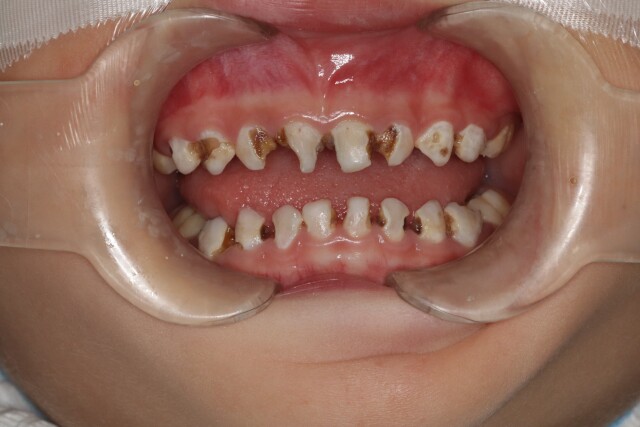

“本想着孩子以后反正还会换牙,就没有重视起来。” 近日,4岁的女孩乐乐因为牙疼不止,被妈妈带到湖南省儿童医院口腔科就诊,经该院口腔科副主任游弋检查发现乐乐竟有10多颗龋齿。乐乐妈妈说,乐乐特别爱吃甜食,又不爱刷牙,刷牙总是断断续续的,

游弋第一时间对乐乐进行了口腔评估,在完善麻醉术前检查和评估后,为乐乐实施了全麻下患牙一次性舒适化治疗,包括龋齿充填、根管治疗、牙冠修复以及涂氟等治疗。3小时后,乐乐顺利完成治疗,乐乐妈妈也长舒了一口气:“原以为乐乐坏了这么多颗牙,可能需要跑医院很多趟,而且孩子对看牙极不配合,想想就头痛,现在好了,一次就全部解决了。”在医院观察4小时后,乐乐开心地跟妈妈回家了。

乐乐治疗前